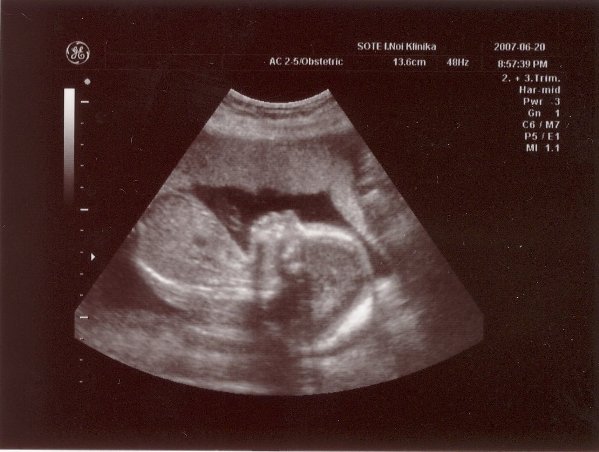

Voltam ma NST-n. Minden okés volt, bár a bébi nem nagyon akart mocorogni... Szerintetek is normális ugye, hogy mostmár kevesebbet mocorog? Főleg, ha megtalálta a helyét fejjel lefelé...?!

Gyönyörű a kislányod a képen, annyira csodálatos, hogy ennyire látszik mindene! HIdd el, nemsokára mindannyian a kezünkbe tarthatjuk őket, és mi leszünk a legboldogabbak a világon!!!

Nagyon szép az uh-os képed!

De irigykedek rá, hogy láttad a haját! Én is hajasbabát szeretnék!!!

RAkok nektek egy mai pocak képet